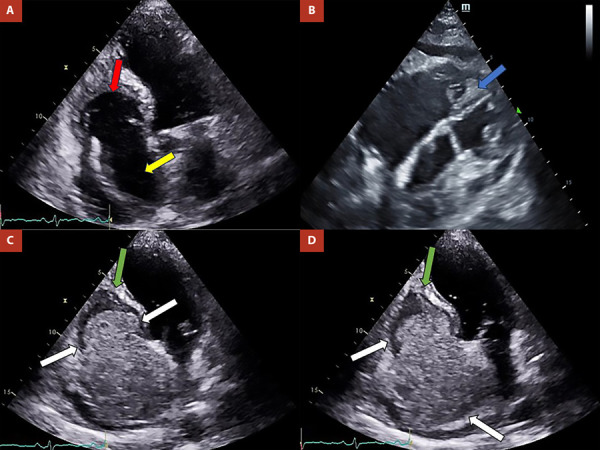

心内膜肌纤维化或戴维斯病是一种罕见的限制性心肌病的原因。它的特点是纤维物质沉积在心内膜,导致快速进行性心力衰竭。它最常影响两个心室,孤立地累及右心室是最不常见的形式。该疾病的临床表现以右心衰症状为基础,但也可能出现心律失常和传导障碍。治疗是由充血的管理和有症状患者的手术干预决定的。我们提出了第一例分离自哥伦比亚右心室的心内膜肌纤维化,我们描述了临床,病因学,影像学和管理特点,以便向医学界提供对这种疾病的大致理解,重点是一种不寻常的表现方式。

Endomyocardial fibrosis or Davies disease is a rare cause of restrictive cardiomyopathy. It is characterized by the deposit of fibrous material in the endocardium that leads to quickly progressive heart failure. It most frequently affects both ventricles, with isolated involvement of the right ventricle being the least common form. The clinical presentation of this entity is based on symptoms of right heart failure, although arrhythmias and conduction disorders may also be present. The treatment is determined by the management of congestion and surgical intervention in symptomatic patients. We present the first case of endomyocardial fibrosis isolated from the right ventricle in Colombia, we describe the clinical, etiological, imaging and management characteristics in order to deliver to the medical community an approximate understanding of this disease focusing on an unusual way of presentation.